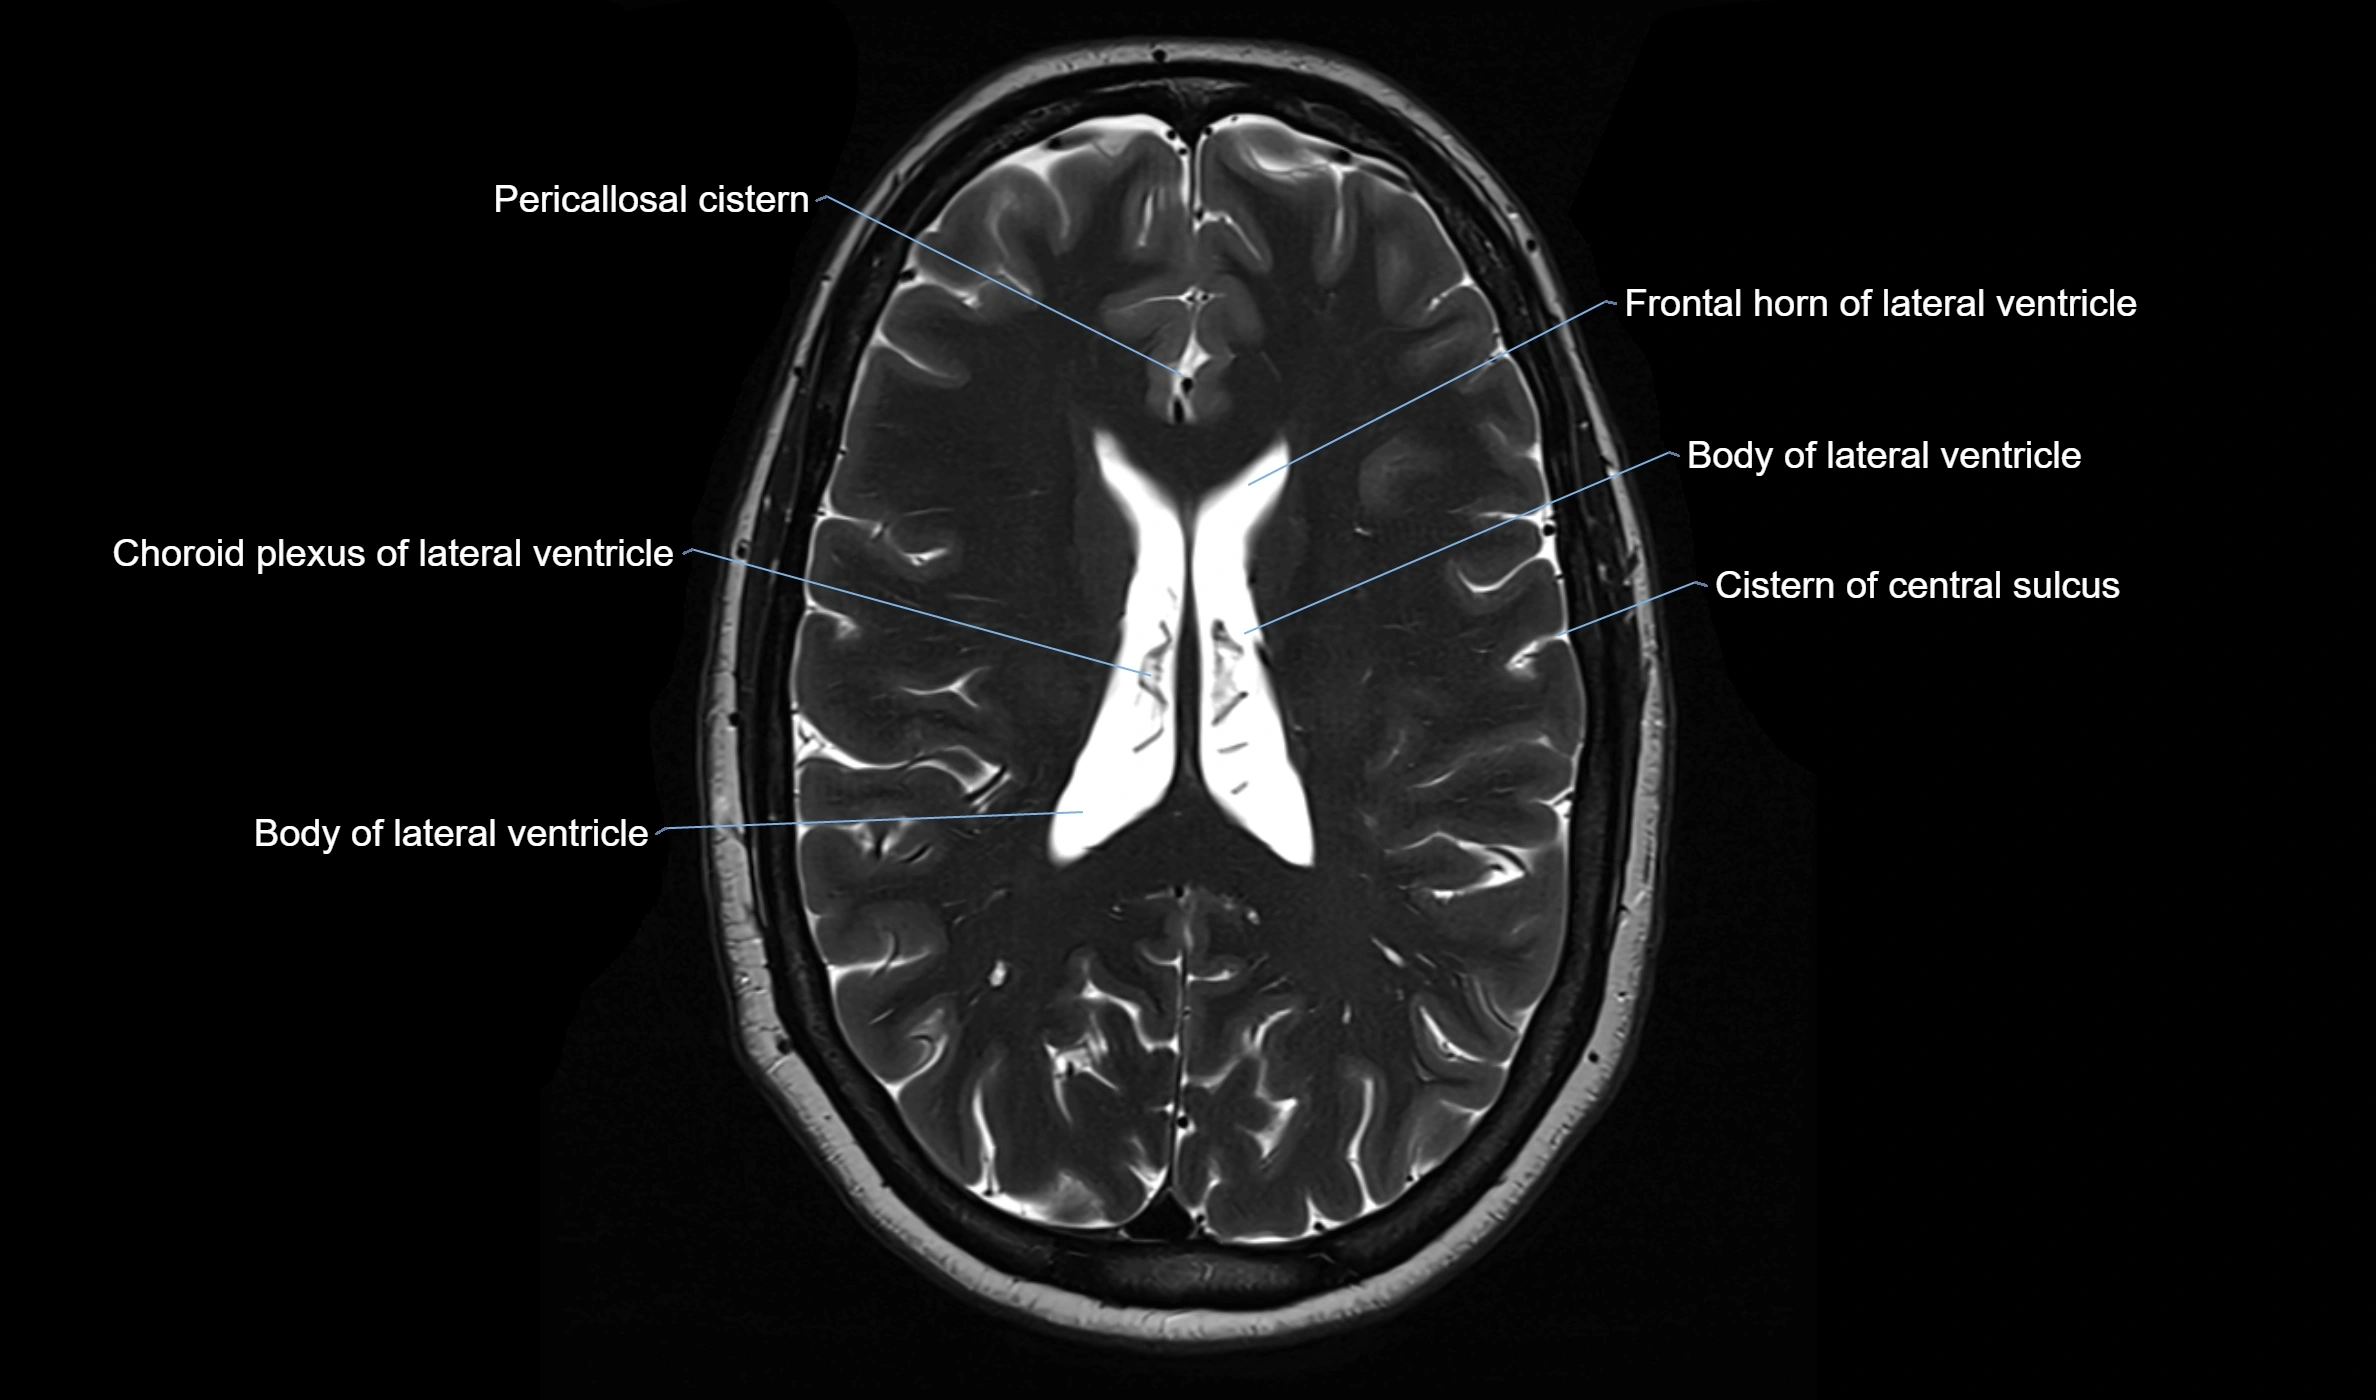

MRI images

image